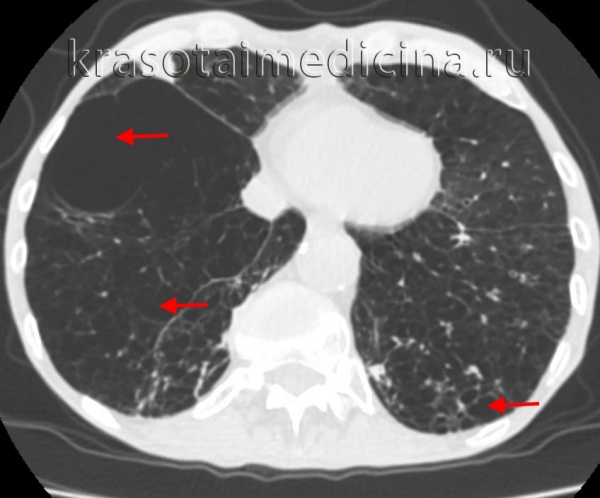

Буллезная эмфизема легкого – это локальные изменения легочной ткани, характеризующиеся деструкцией альвеолярных перегородок и формированием воздушных кист диаметром более 1 см (булл). При неосложненном течении буллезной эмфиземы легких симптомы могут отсутствовать вплоть до возникновения спонтанного пневмоторакса. Диагностическое подтверждение буллезной эмфиземы легких достигается с помощью рентгенографии, КТ высокого разрешения, сцинтиграфии, торакоскопии. При бессимптомной форме возможно динамическое наблюдение; в случае прогрессирующего или осложненного течения буллезной болезни легких проводится хирургическое лечение (буллэктомия, сегментэктомия, лобэктомия).

Буллезная эмфизема легкого – ограниченная эмфизема, морфологическую основу которой составляют воздушные полости (буллы) в паренхиме легкого. В зарубежной пульмонологии принято различать блебы (англ. «blebs» - пузыри) - воздушные полости размером менее 1 см, расположенные в интерстиции и субплеврально, и буллы - воздушные образования диаметром более 1 см, стенки которых выстланы альвеолярным эпителием. Точная распространенность буллезной эмфиземы легкого не определена, однако известно, что данное заболевание служит причиной спонтанного пневмоторакса в 70–80% случаев. В литературе буллезную эмфизему легких можно встретить под названиями «буллезная болезнь», «буллезное легкое», «ложная/альвеолярная киста», «синдром исчезающего легкого» и др.

Кроме этого, буллы могут быть солитарными и множественными, одно– и двусторонними, напряженными и ненапряженными. По распространенности в легком дифференцируют локализованную (в пределах 1-2-х сегментов) и генерализованную (с поражением более 2-х сегментов) буллезную эмфизему. В зависимости от размера буллы могут быть мелкими (диаметром до 1 см), средними (1-5 см), крупными (5-10 см) и гигантскими (10-15 см в диаметре). Буллы могут располагаться как в неизмененном легком, так и в легких, пораженных диффузной эмфиземой.

Диагностика буллезной эмфиземы легких основывается на клинических, функциональных и рентгенологических данных. Курация больного осуществляется пульмонологом, а при развитии осложнений – торакальным хирургом. Рентгенография легких не всегда эффективна в выявлении буллезной эмфиземы легких. В то же время, возможности лучевой диагностики существенно расширяет внедрение в практику КТ высокого разрешения. На томограммах буллы определяются как тонкостенные полости с четкими и ровными контурами. При сомнительном диагнозе удостовериться в наличии булл позволяет диагностическая торакоскопия.